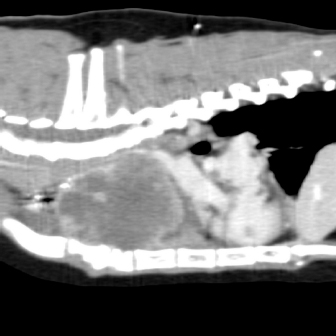

On physical examination, the cat had an unkept coat, reduced respiratory sounds cranially, and persistent stridor, but was otherwise bright and ambulatory. Computed tomography (CT) was performed using a Phillips Brilliance six slice CT. Multiphase contrast-enhanced CT images of the head, thorax, and abdomen were acquired with the cat in sternal recumbency (Figs. 1 and 2). A cranial mediastinal mass measuring 60 × 40 mm causing dorsal tracheal displacement toward the right was identified. With contrast administration, there was moderate enhancement of the periphery (+60 Hu) and poor central enhancement (+10 Hu). There was moderate to marked compression of the cranial vena cava, with a focal intraluminal contrast-filling defect at the cranial aspect of the vena cava just caudal to the mass. Here, the path of the cranial vena cava could not be completely traced, suggesting almost complete compression or invasion. There was no evidence of subcutaneous edema of the head or cervical region. Moderate volume of pleural fluid was bilaterally present. Multifocal, slightly branching soft tissue conglomerates largely following the bronchi of the caudal lobes toward the apex was noted, most likely to be bronchial disease with bronchiolar consolidation. Pulmonary metastatic neoplasia was considered to be unlikely. Surgical resection in the form of debulking was recommended on the basis that the large cranial mediastinal mass was most likely the cause of the cat’s clinical signs, and that reduction of gross disease should improve survival time as well as being more responsive to adjunctive treatment with chemotherapy. The cat was then started on mirtazapine (1.875 mg orally every 48 hours) and prednisolone (5 mg orally every 24 hours).

Fig. 1. Computerized tomography of the cranial mediastinal mass (sagittal plane).